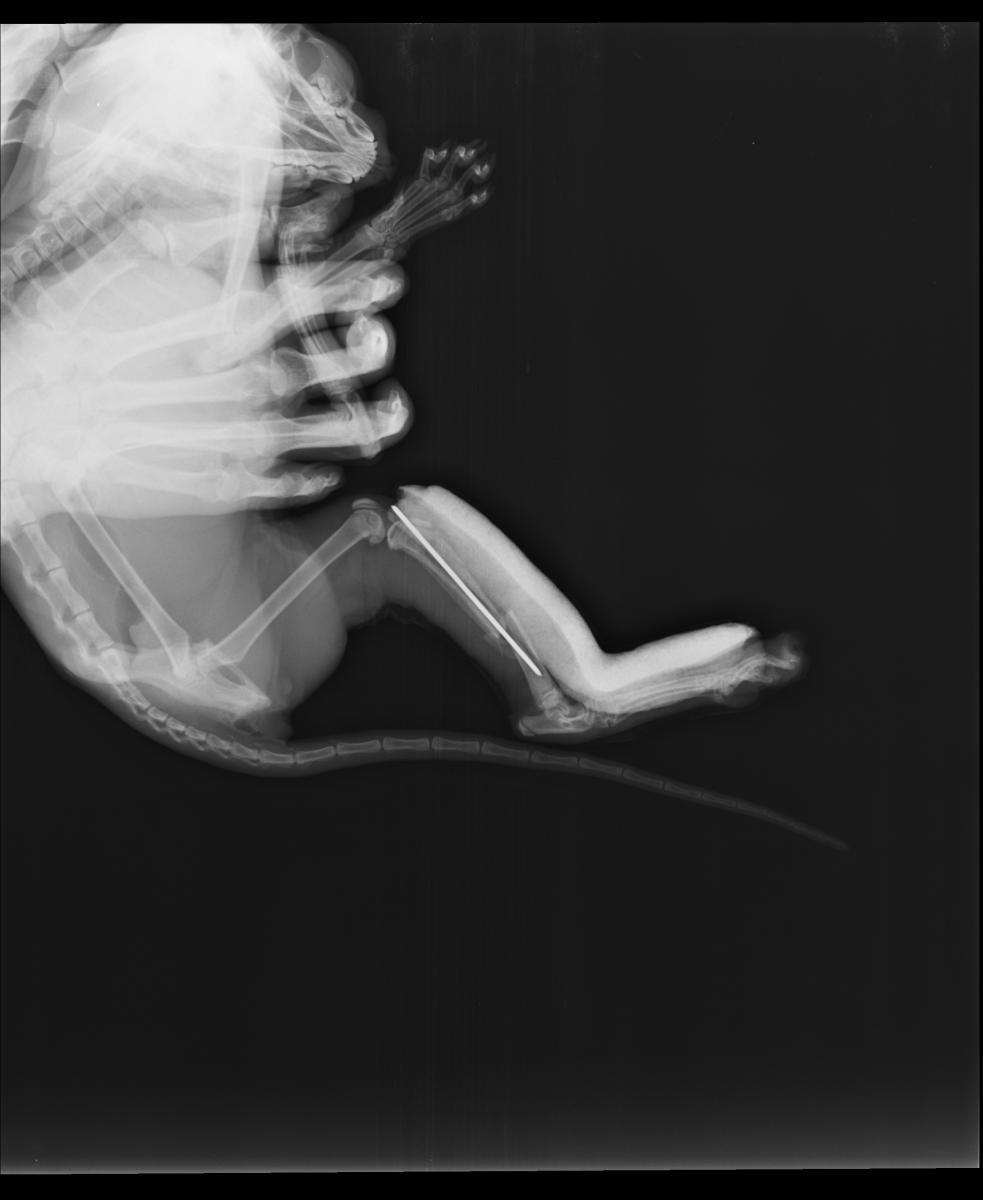

cat_X-ray_photo.jpg

Судя по снимку, кошке однозначно показана операция.

Существует ли альтернатива операции? "Оставить всё как есть" - не рассматриваю, т.к. кошка должна нормально ходить, бегать и прыгать.

Врач сообщил, что при таком характере перелома, как на снимке выше, остеосинтез желательно проводить накостными пластинами. Он же сказал, что в Подольске с пластинами никто не работает.

Другой врач высказал сомнение в возможности использования пластин из-за миниатюрных размеров кости.